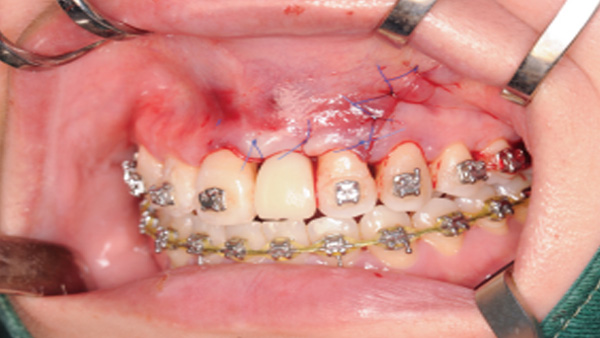

覆蓋所有牙位、即刻種植、即拔即種、全口無牙頜種植